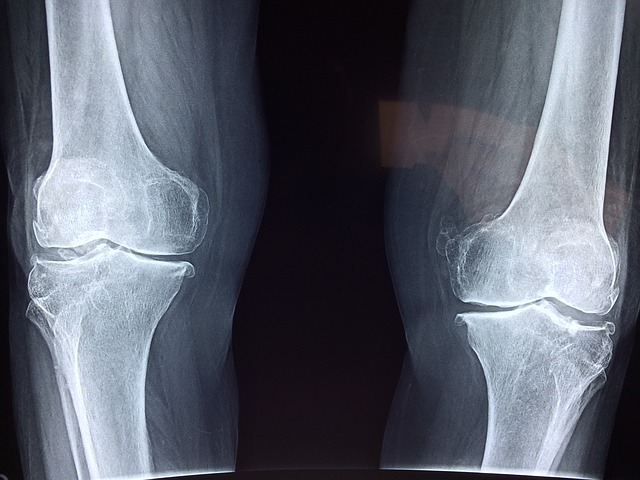

Az ízületi betegségeknek számtalan típusa ismert, melyeket két fő csoportba sorolhatunk. Az egyikbe tartoznak az akut és krónikus gyulladások (arthritisek), a másik nagy csoportba pedig az artrózisok sorolhatóak, vagyis az ízületi kopások. Az arthritis baktérium-, vírusfertőzés vagy anyagcsere-zavar miatt alakulhat ki. Artrózis a mozgásszegény életmód, a túlsúly vagy egy sérülés kapcsán fejlődhet ki bármelyik ízületben.

Az ízületeket védő porcok kb. 80%-a vízből áll, a maradék 20% pedig vázfehérjékből és cukor-fehérje vegyületekből. Kisebb sérülések esetén a porcsejtek képesek kijavítani a károsodásokat, azonban hosszabb ideig fennálló probléma esetén erre képtelenek. Ezáltal megváltozik a porc összetétele, elveszíti rugalmasságát, simaságát és regeneráló képességét. Egy idő után a felülete repedezni kezd, durvává válik, majd darabok szakadnak le róla. Az ízületekben ezáltal gyulladások keletkeznek, így még jobban károsodik a porc. Ez a kopásos folyamat végül a porc teljes elhalásához vezethet, ekkor a csont csonthoz dörzsölődik, ami nagy fájdalmakat okoz, eközben a csont megvastagodik és ettől az ízületek elmerevednek.